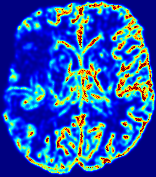

Slice #1Slice #2Slice #3Slice #4Slice #5Slice #6Dgtsuperscript𝐷gtD^{\text{gt}}Refer to captionRefer to captionRefer to captionRefer to captionRefer to captionRefer to captionDestsuperscript𝐷estD^{\text{est}}Refer to captionRefer to captionRefer to captionRefer to captionRefer to captionRefer to captionRefer to caption0.300.300.300.240.240.240.180.180.180.120.120.120.060.060.060.000.000.00(mm2/s)𝑚superscript𝑚2𝑠(mm^{2}/s)𝐕est𝟐subscriptnormsuperscript𝐕est2\|\bf{V}^{\text{est}}\|_{2}Refer to captionRefer to captionRefer to captionRefer to captionRefer to captionRefer to captionRefer to caption0.00300.00300.00300.00240.00240.00240.00180.00180.00180.00120.00120.00120.00060.00060.00060.00000.00000.0000(mm/s)𝑚𝑚𝑠(mm/s)

Figure 15: PIANO identifiability testing: diffusion imaging via advection-diffusion. Top row shows Dgtsuperscript𝐷gtD^{\text{gt}} used for simulating ground truth pure diffusion. Rows below show the estimated Destsuperscript𝐷estD^{\text{est}} and 𝐕est2subscriptnormsuperscript𝐕est2\|{\bf{V}}^{\text{est}}\|_{2} on corresponding slices. Note that the plotted value scale for 𝐕est2subscriptnormsuperscript𝐕est2\|{\bf{V}}^{\text{est}}\|_{2} is 0.01 of that for Dgtsuperscript𝐷gtD^{\text{gt}} and Destsuperscript𝐷estD^{\text{est}}.

Similarly, we test the behavior of PIANO when estimating both advection and diffusion from a pure diffusion-driven process. The goal is to determine if PIANO is able to recognize that there is only diffusion governing the given concentration time-series. We use the same ‘Diffusion Imaging’ data simulation of Sec. 4.2.1 as the concentration dataset, PIANO estimates both velocity 𝐕estsuperscript𝐕est{\bf{V}}^{\text{est}} and diffusivity Destsuperscript𝐷estD^{\text{est}}. Estimation results in Fig. 15 confirm PIANO’s identifiability again: the estimated 𝐕est2subscriptnormsuperscript𝐕est2\|{\bf{V}}^{\text{est}}\|_{2} is almost invisible compared to Destsuperscript𝐷estD^{\text{est}}, even plotted with a 1%percent11\% value range compared to that for Destsuperscript𝐷estD^{\text{est}}. On the other hand, Destsuperscript𝐷estD^{\text{est}} achieves comparable estimation performance as ‘Diffusion Imaging via Diffusion’ in which PIANO predicts Destsuperscript𝐷estD^{\text{est}} alone (shown in Fig. 13).